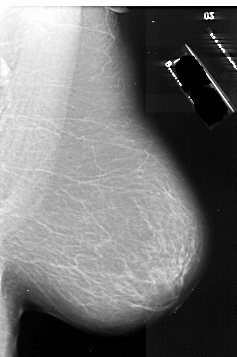

A_1011_1.LEFT_MLO

LEFT_MLO LINES 6586 PIXELS_PER_LINE 4786 BITS_PER_PIXEL 16 RESOLUTION 42 OVERLAY